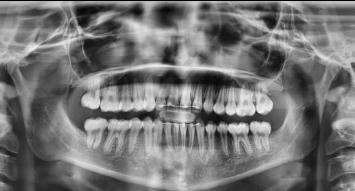

Estudios radiográficos de inicio

En la radiografía lateral de cráneo se observa un crecimiento hiperdivergente y la clase II esquelética con un Witts de 2 mm (Figura 7). En panorámica, 31 dientes permanentes presentes con terceros molares impactados y ausencia de OD 48 (Figura 8).

Figura 7. Lateral de cráneo. Figura 8. Radiografía panorámica.